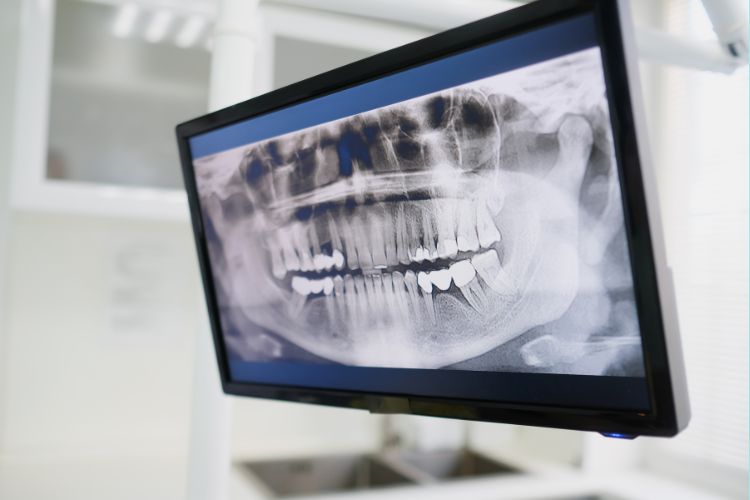

Найнадійніший спосіб — рентгенологічне дослідження. Звичайний огляд не завжди дозволяє побачити прихований зуб, тому лікар може призначити:

- Ортопантомограму (панорамний знімок) — показує всі зуби, включно з тими, що не прорізалися.

- КТ (комп’ютерну томографію) — детальніше зображення для оцінки положення зуба відносно нервів і кісткової тканини.

Таке дослідження дозволяє стоматологу визначити, чи є сенс зберігати зуб, чи його потрібно видаляти.